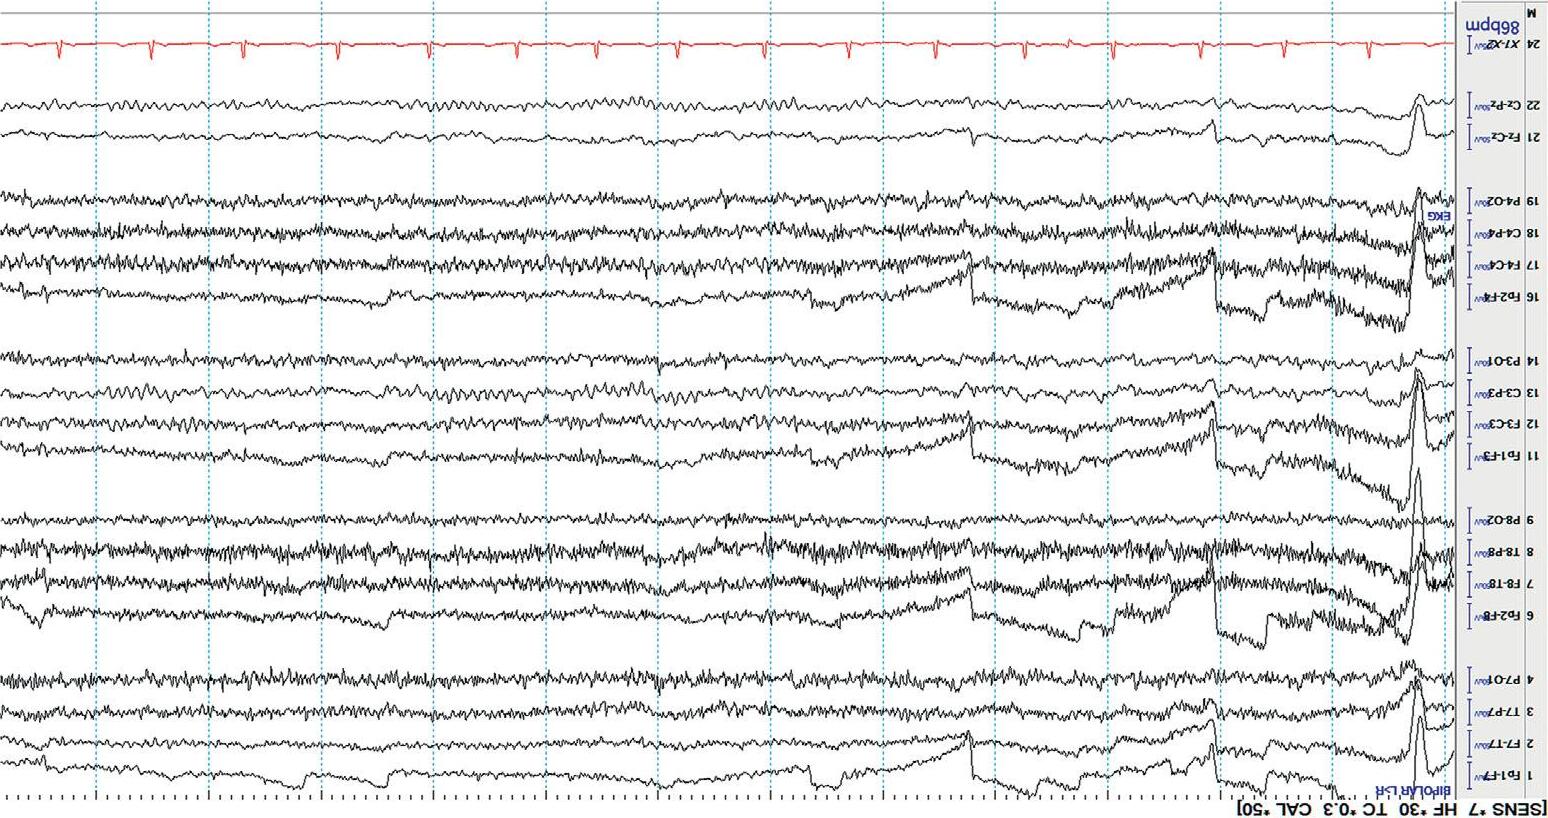

Mostdisplaysshow10or15secondsperpageofEEG. Figure1.5 showsa typicaldisplayusingthelongitudinalbipolarmontagewithexcessivemuscle artifactbefore(a)andafter(b)applicationof30Hzhighfrequencyfilter.

Figure1.5(a) EEGwithHFFsetto70Hz.